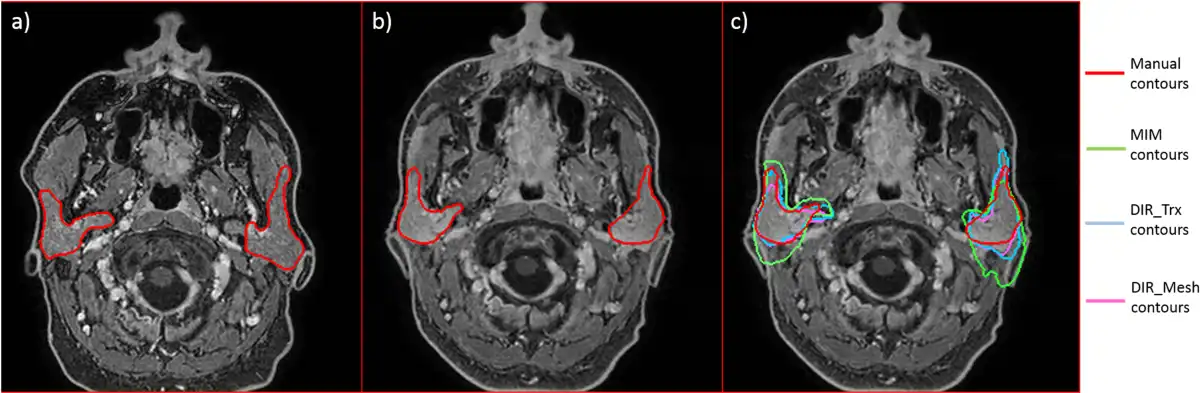

In few cases, contour propagation failed, in particular when MIM was considered; this happened when big deformations and changes in parotid shape occurred (see Figure 5A and B, where a clear difference in head and parotid shape is shown). In this case, MIM had a greater difficulty in recovering parotid contours (green line in Figure 5C), with respect to the other 2 methods (light blue and purple line in Figure 5C).

Figure 5

Example of a failed contour propagation, especially for MIM (green line). A, Magnetic resonance imaging (MRI) acquired before radiation therapy (RT) with manual parotid contours. B, Magnetic resonance imaging acquired after RT with manual parotid contours. C, Magnetic resonance imaging acquired after RT with manual and deformed contours.